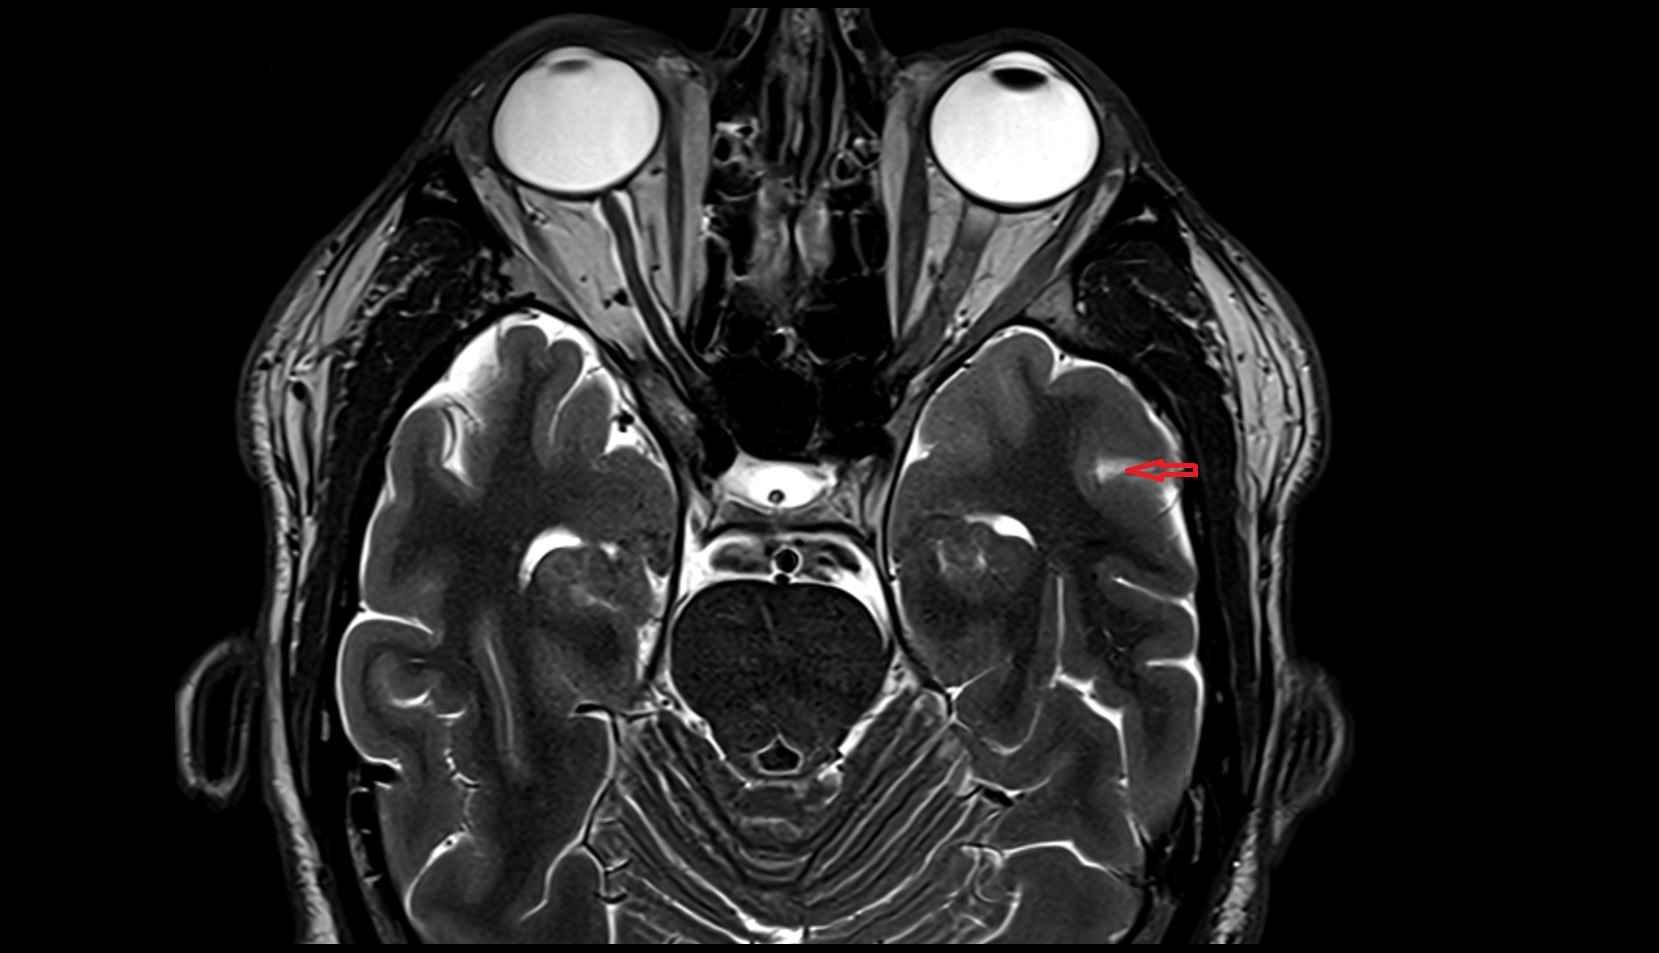

- Cerebellum